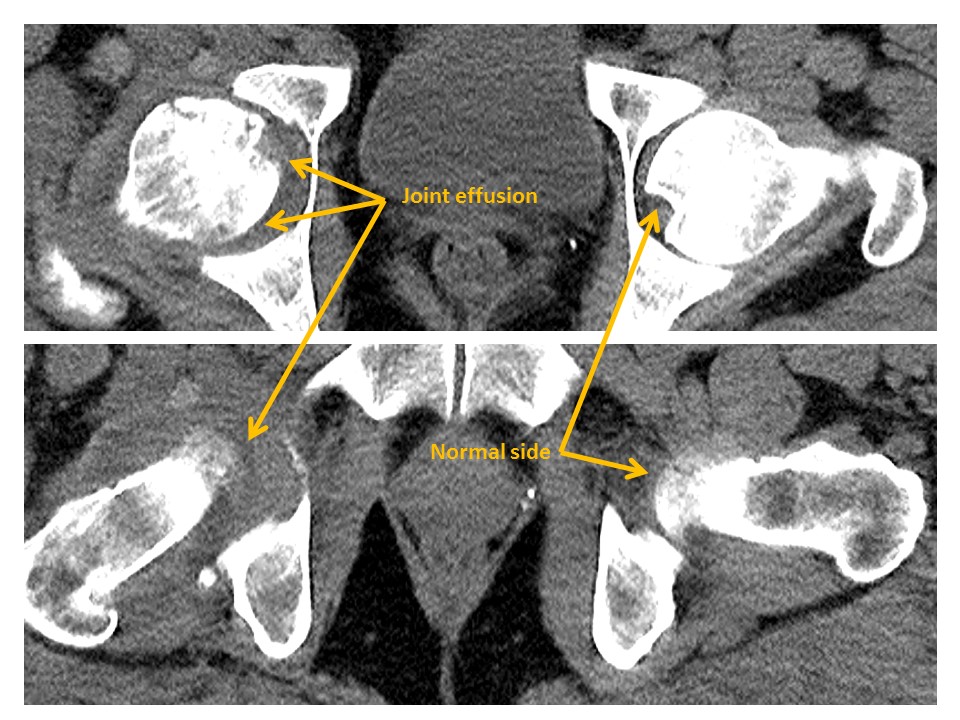

There are hip joint effusions. |

No | NA |